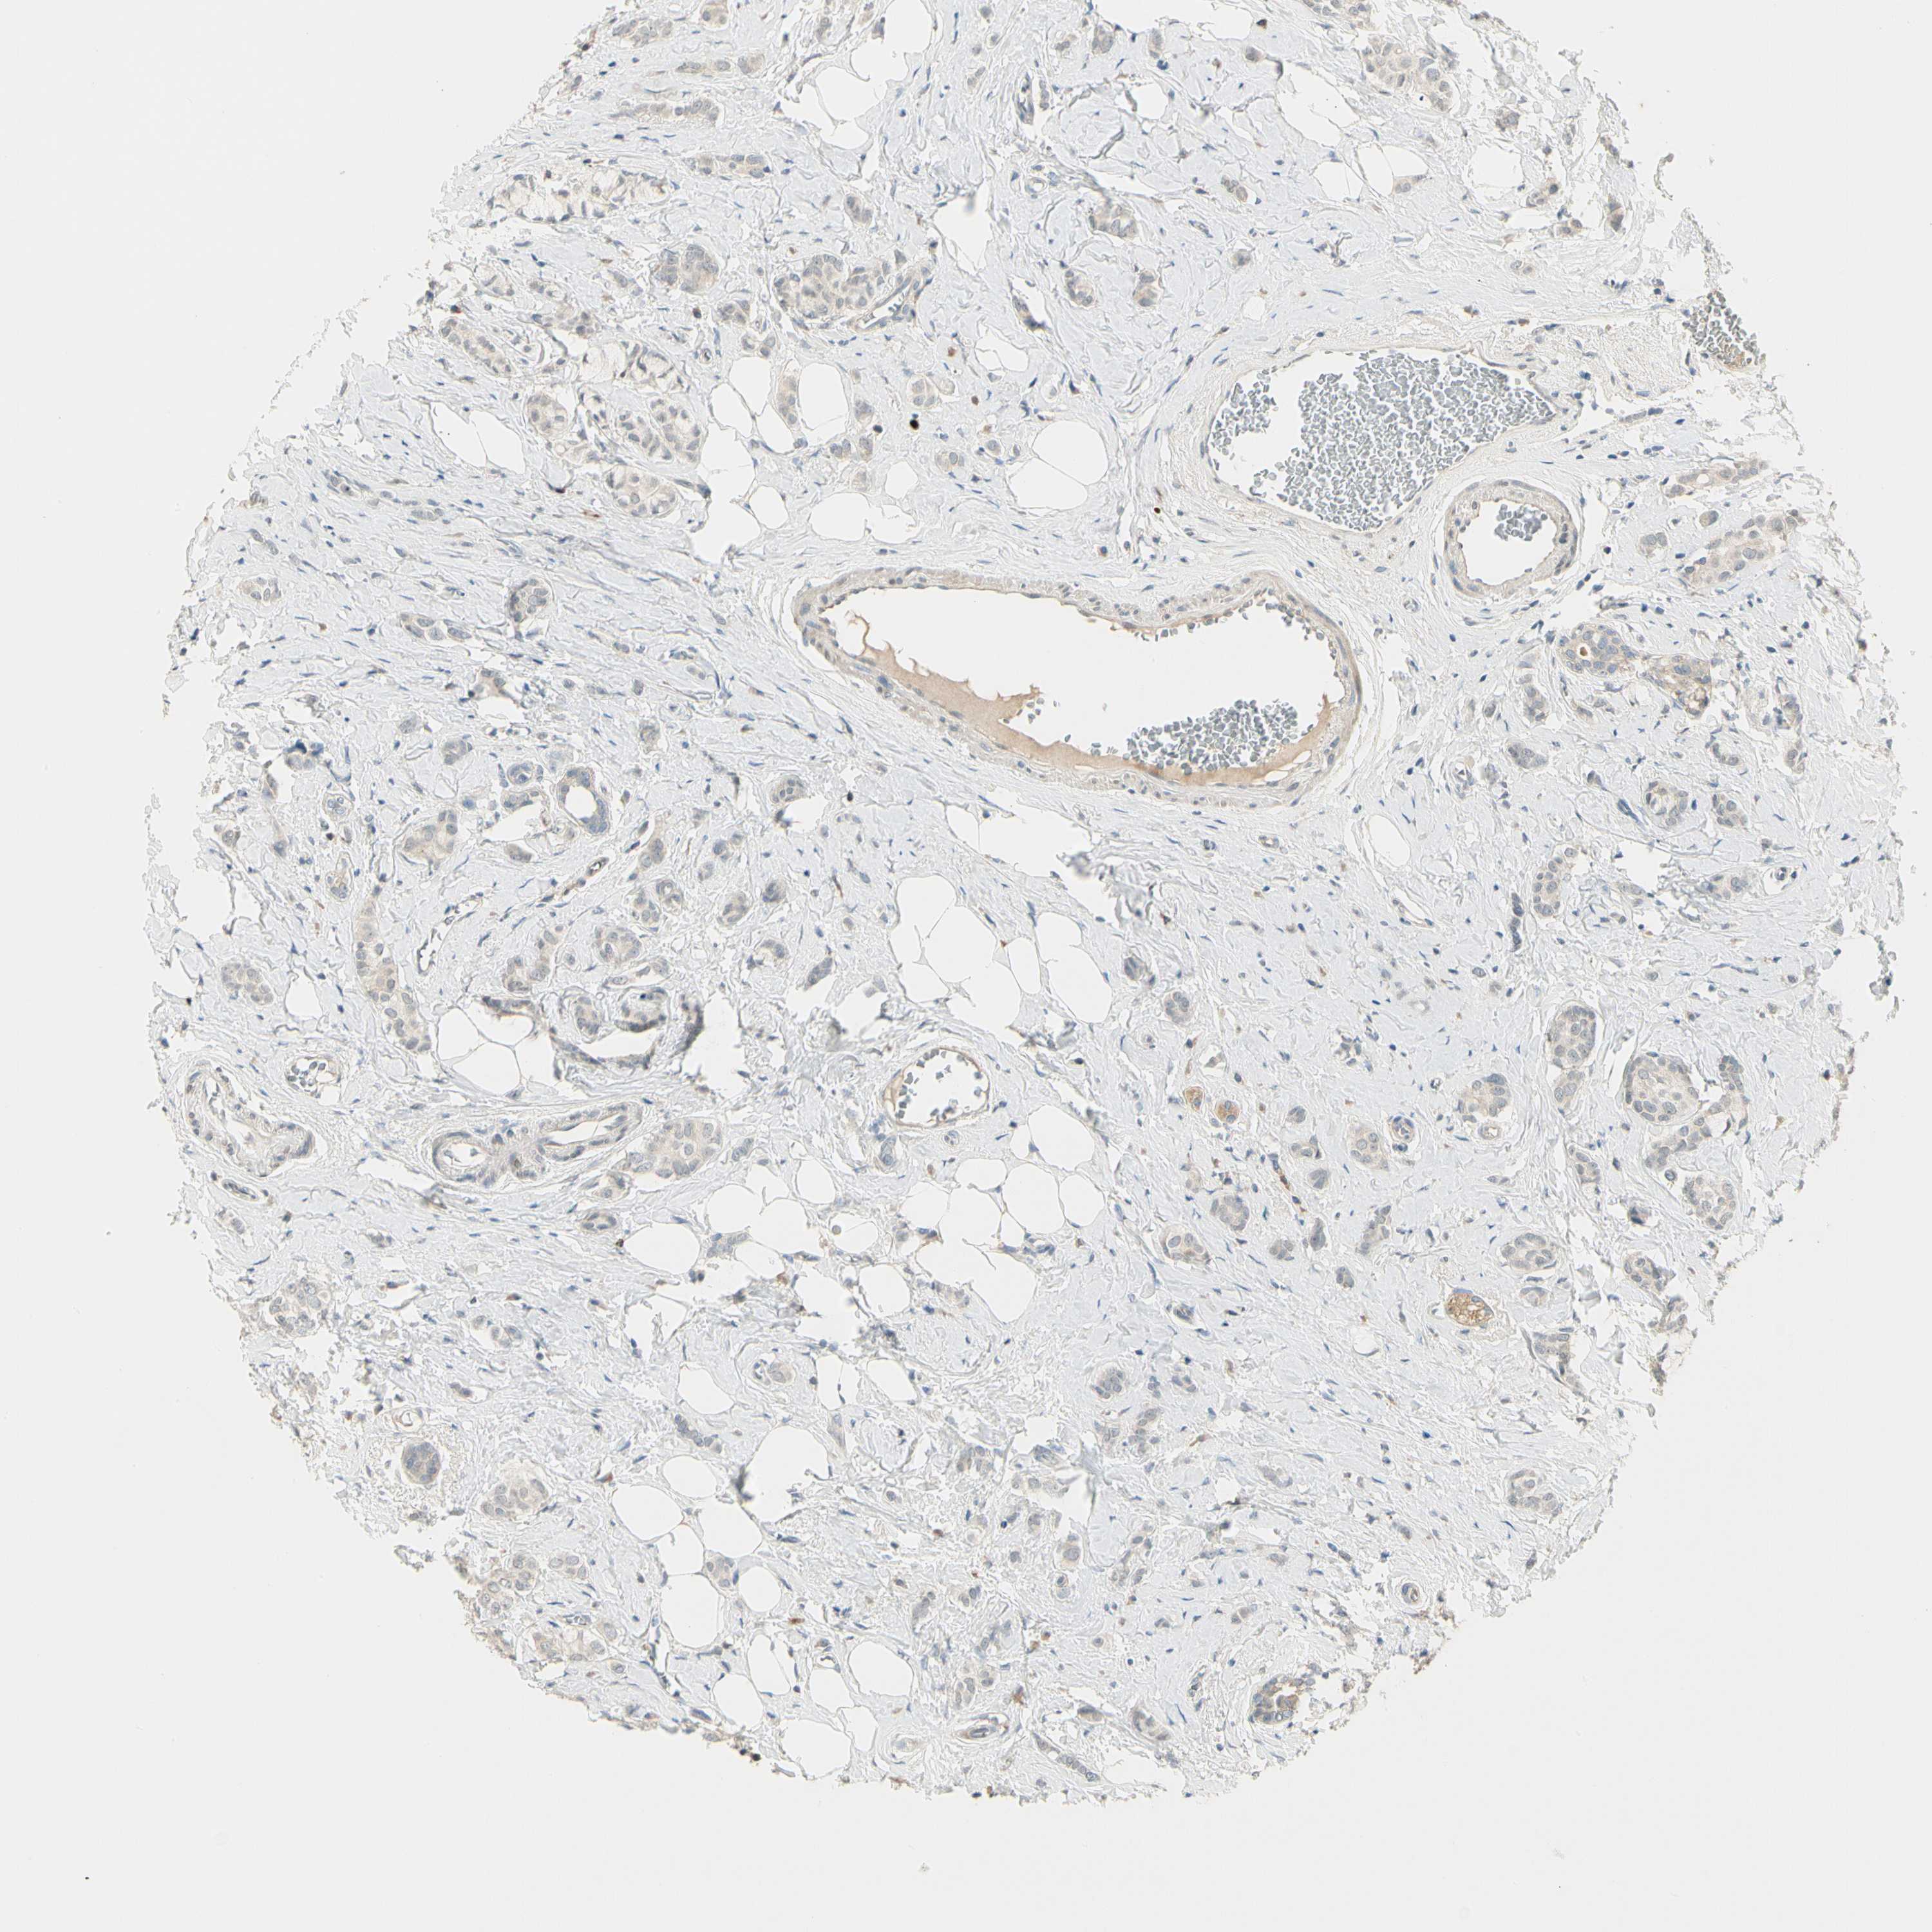

BRCA TCGA BRCA VALIDATION PROTEIN EXPRESSION